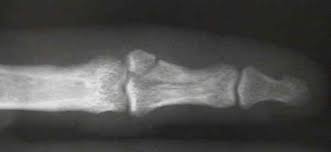

Middle phalangeal fractures proximal to the FDS insertion have an apex dorsal angulation whereas fractures distal to the FDS insertion have an apex volar angulation as shown in the figure. Undisplaced or minimally displaced fractures of the diaphysis of the middle phalanx can be treated non-operatively.

Nonoperative Treatment For Shaft Transverse